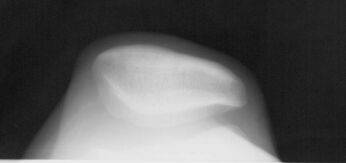

На боковом снимке профиль надколенника имеет две задние линии. Одна из них соответствует гребню надколенника, другая, более плотная, соответствует его наружному краю. Расстояние между этими двумя линиями и является надколенниковым индексом, который в норме составляет 5 мм (рис. 4). Значения ниже или равные 2 мм говорят в пользу нестабильности, которая, однако, может быть транзиторной, исчезающей при более сильном сгибании, чем на 15 или 30°.

Рисунок 4. Надколенниковый индекс. Объяснения в тексте.

Преимущество бокового снимка, по сравнению с аксиальными проекциями, связано с возможностью анализа движения надколенника в самом начале сгибания от 0 до 30°, когда он начинает внедряться в трохлеарное устье дистального эпифиза бедренной кости. В этот момент можно оценить глубину межмыщелковой борозды и установить дисплазию трохлеи, которая может оказаться причиной нестабильности.